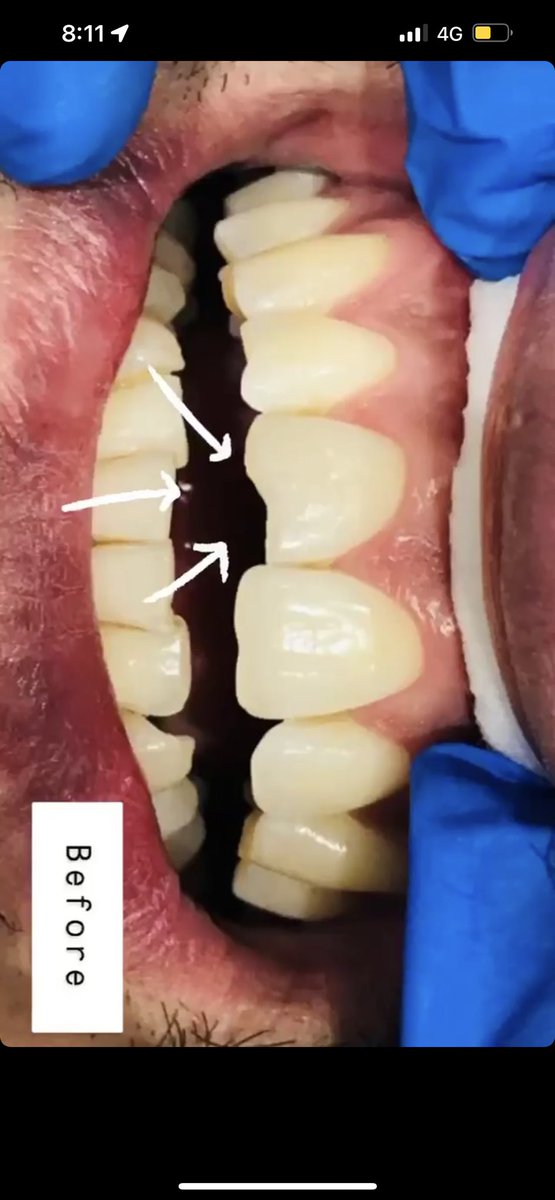

حشوه اماميه تجميليه ✨ حشوه صغيره تعمل فرق كبير في الابتسامه ✨ من شغلي .. #اسنان #حشوات_تجميليه